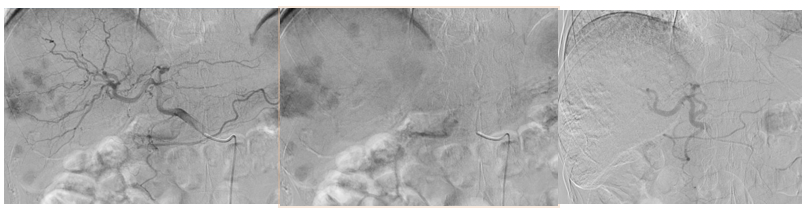

2021年8月30日行第7次cTACE,也是末次TACE:肝内肿瘤供血动脉以及肿瘤染色明显减少、好转,对肿瘤血管进行超选择化疗栓塞。患者进入靶免维持治疗阶段,定期复查,病情稳定。

2022年4月27日,术后2年余复查上腹部CE-MRI:肝内肿瘤病灶继续消退,无明显活性,无新发肿瘤病灶(图8);AFP降至正常范围内2.19ng/ml。按照mRECIST标准基本达到完全缓解(CR)。

图7.2022年4月27日上腹部CE-MRI